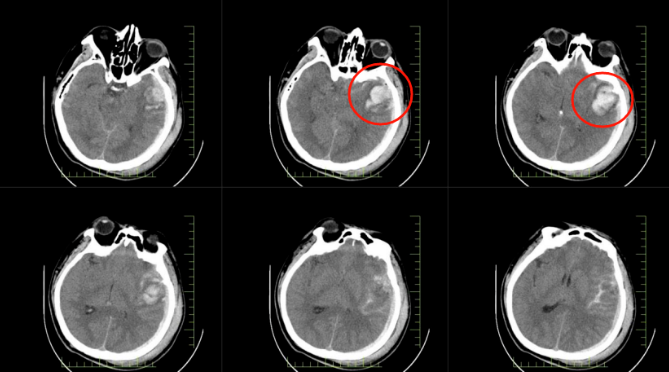

患者郭先生因高處墜落,送達(dá)醫(yī)院時(shí)已陷入昏迷。經(jīng)急診全面檢查,被確診為顱腦損傷重型、腦挫裂傷伴腦內(nèi)血腫、創(chuàng)傷性蛛網(wǎng)膜下腔出血等多項(xiàng)嚴(yán)重病癥。顱內(nèi)出血、顱壓驟升,每一項(xiàng)診斷都如同高懸的達(dá)摩克利斯之劍,威脅著患者的生命。

*患者顱內(nèi)出血影像圖

*患者顱內(nèi)術(shù)后影像圖